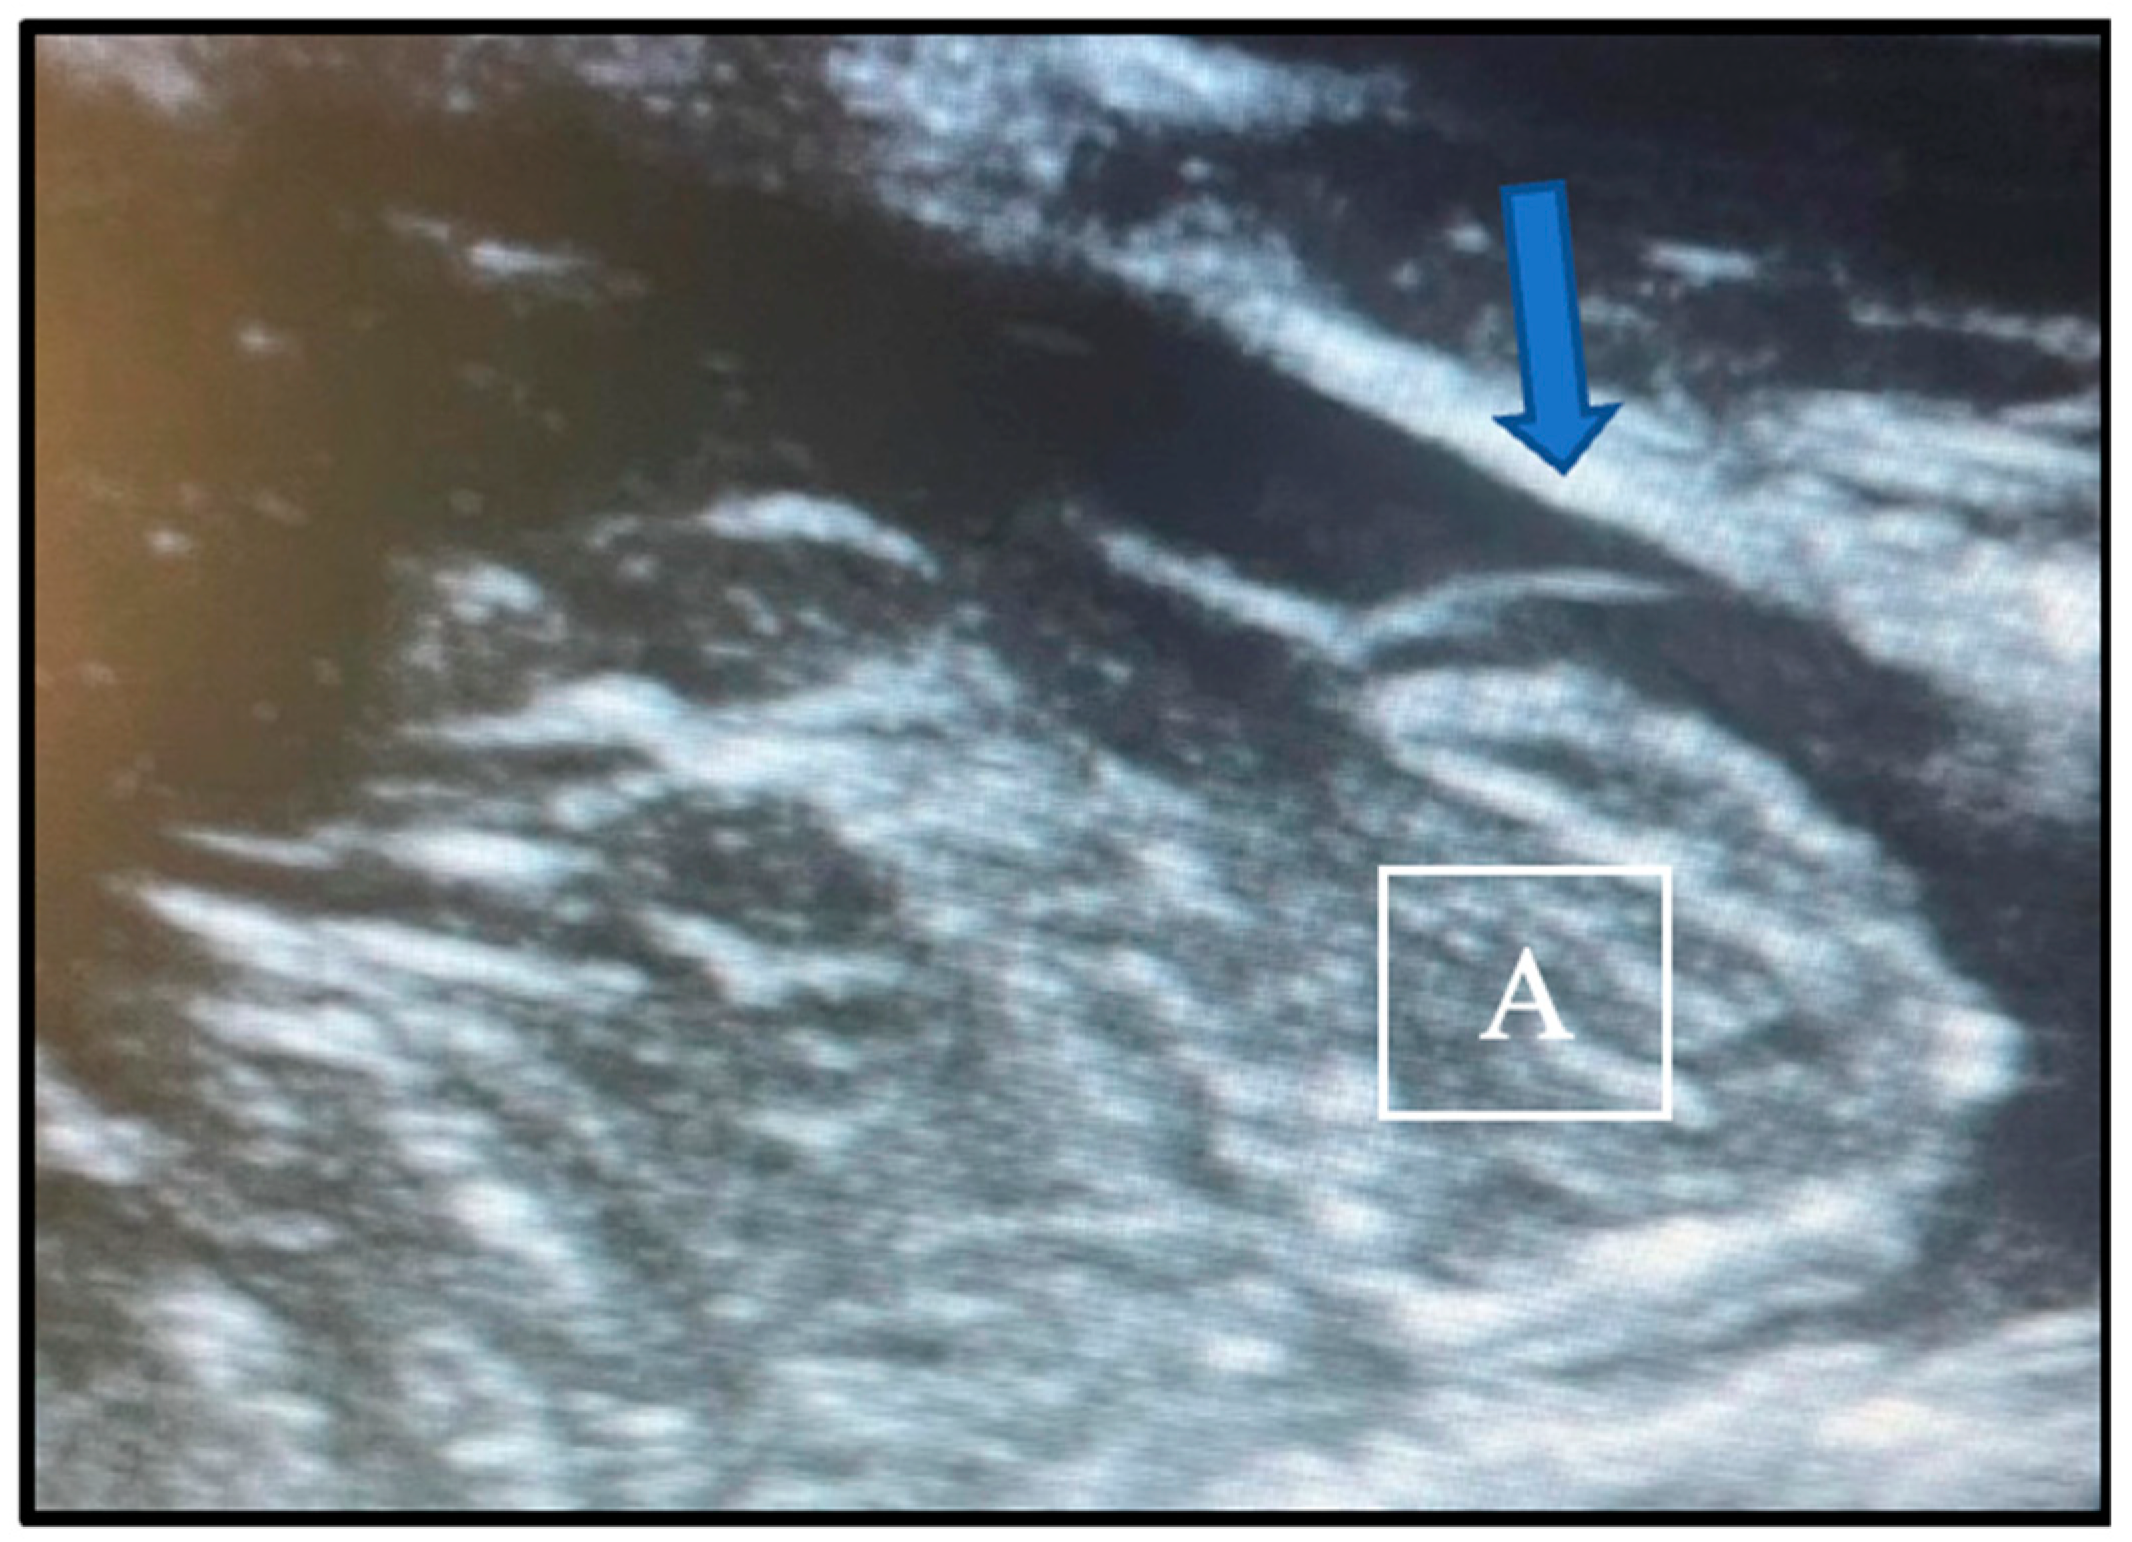

We tailored the procedure of choice to the individual patient. In the presence of spinal syringomyelia, we always performed a dural and osteo-ligamentous decompression. In all other situations, however, we first performed a bony and ligamentous decompression and use intraoperative ultrasonography to evaluate the CSF dynamic and the pulsation pattern of the cerebellar tonsils. If the flow of cerebrospinal fluid in the foramen magnum region was recovered after the bony decompression, the duraplasty would not be carried out. The adequacy of decompression was confirmed by the presence of a CSF layer behind the tonsils and an antero-posterior pattern of tonsillar pulsation. Conversely, the need for dural opening was indicated by the absence of CSF flux and a “piston-like” movement pattern of the tonsils, characterized by vertical pulsations (see Figure 1). We relied solely on qualitative variables, not quantitative measures, with validation through cross-verification by the two operating neurosurgeons.

Figure 1. View of intraoperative ultrasound images depicting the absence of CSF flow (arrow) behind the cerebellar tonsils (A), indicative of the inadequate decompression of the structures.